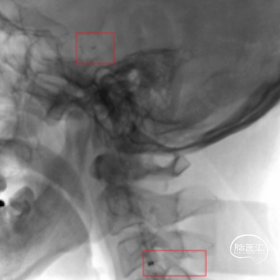

术前CT,ASPECT 8分。

术前CTA检查。

术前造影,BA近端闭塞。

术前造影,LC7次全闭塞。

术前造影,RICA 通过交通动脉向左侧颈内动脉及基底动脉尖代偿供血。